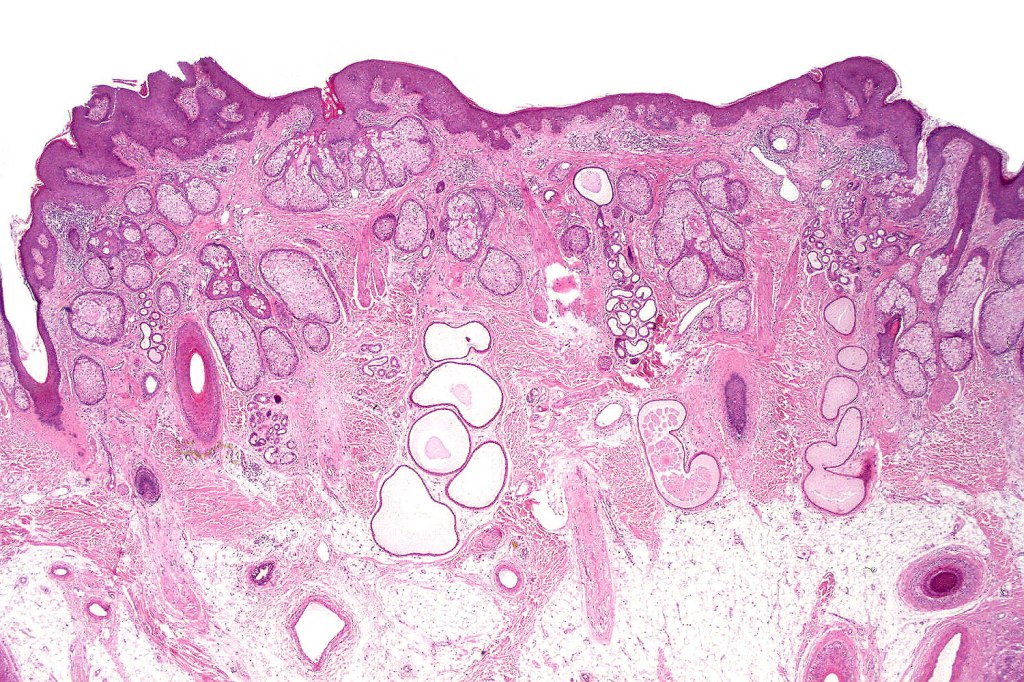

Histological features

•Hamartoma characterized by abnormalities of epidermis, hair follicles, sebaceous glands, apocrine sweat glands & connective tissue

•Epidermis often papillomatous

•Follicular induction is common & sometimes trichoblastomatous foci are evident

•High, increased hyperplastic, sebaceous glands with openings onto the surface epithelium (in. old lesions, they may be absent)

•Reduced hair follicles

•Excessive numbers of apocrine glands